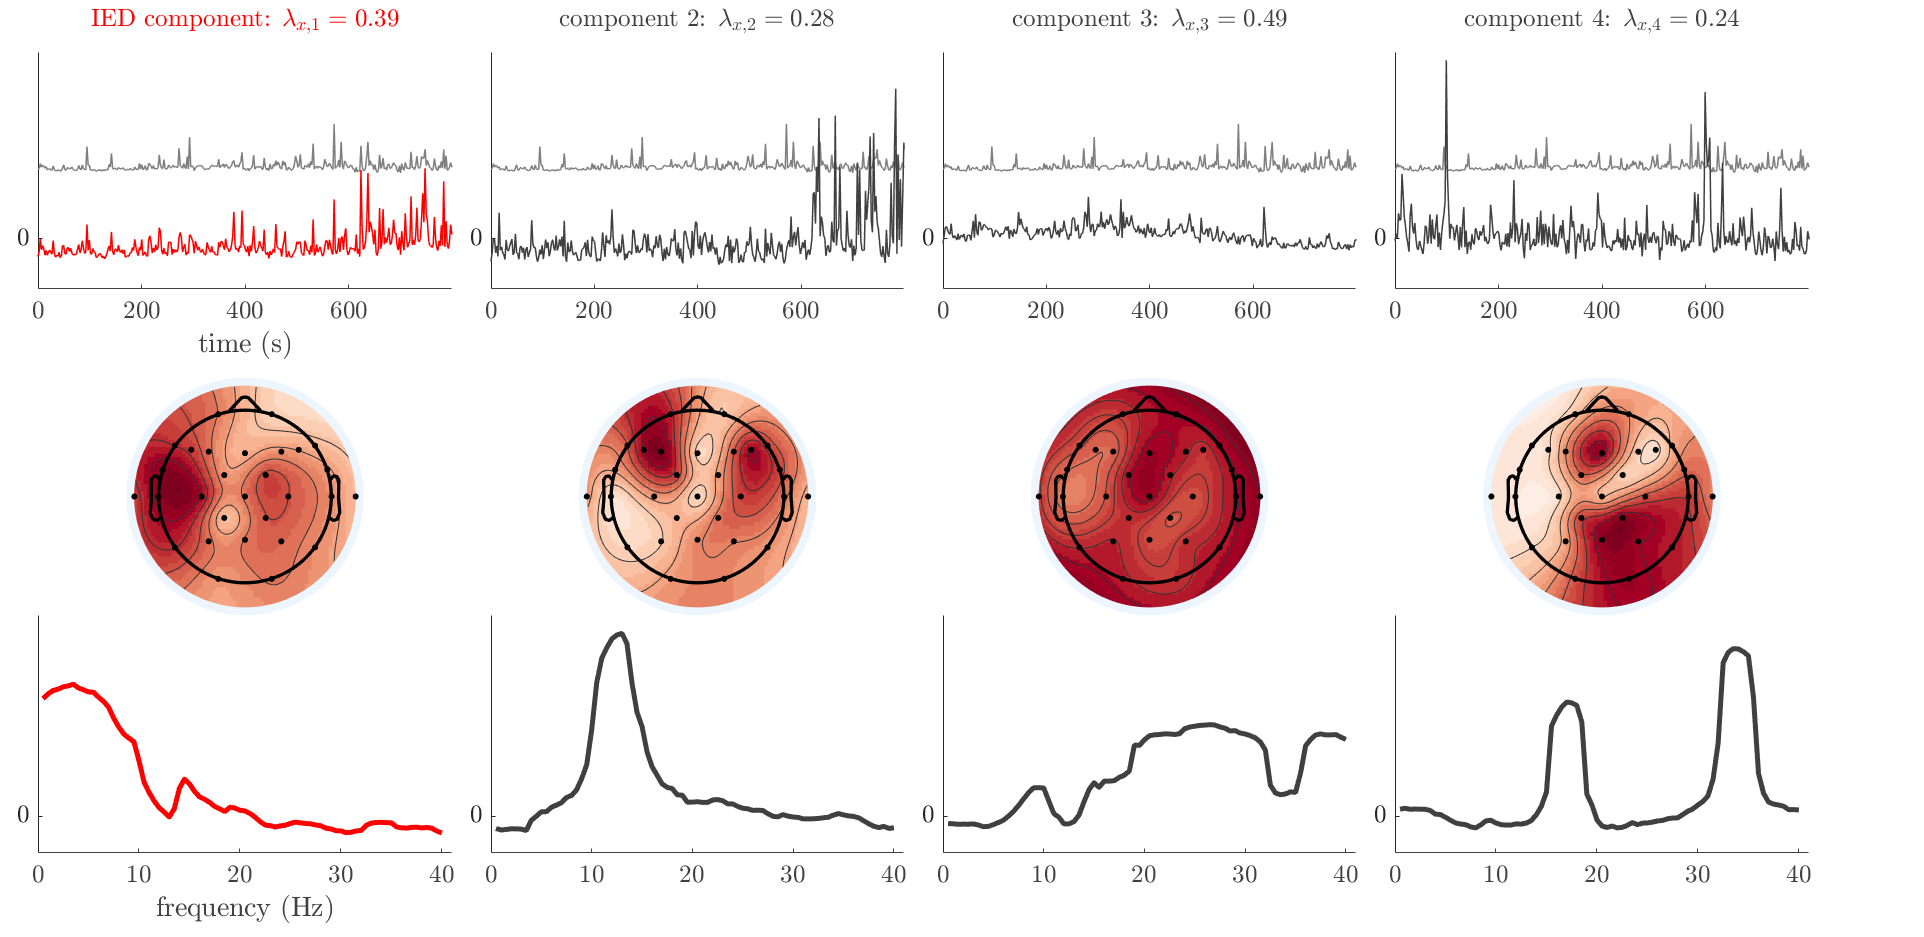

Patient 1

We analyze the solution with sources. Figure 1 shows the EEG signatures and HRF waveforms. One of the sources is highly correlated to the MWF reference (in grey), which was already known from Table B.3. This IED-related source had a typical low-frequency spectrum, which is expected for the typical spike-and-wave interictal discharges. The topography is relatively diffuse, although the highest amplitudes are mostly in the left hemisphere. This is in accordance with the lateralization of ictal onset zone (left temporal lobe, cfr. Table 1). There are some noteworthy observations to be made about some of the other components. The fourth has an unusually sharp spectrum, is mainly localized on two nonadjacent center electrodes, and is sustained for a single period of many seconds Hence, this component likely captured an artifact (of yet unknown origin), although we spotted no large-amplitude changes in the EEG itself. Similarly, the third source is only present at one frontal electrode, and exists in a frequency range above 20 Hz. It might represent a muscle artifact, e.g., due to frowning or twitching of some muscles in the forehead. The HRFs of all ROIs are shown in Figure 1(b). Two of the basis functions seem to have converged to a very similar waveform, which is an unfortunate possibility if two initial HRFs are too close to the same local optimum in their respective parameters. This reduces the expressive power of the basis set, which is clearly visible, since many ROIs have a nearly identical HRF. One of the twenty ROIs with the highest-entropy HRF overlapped the IOZ, although clearly this HRF (bold line) is not among the most dissimilar waveforms for this patient. This is also visible in Figure 2: both the HRF entropy and extremity maps show a small overlap with the delineated IOZ. Despite the good correspondence in the EEG domain, no significant (de)activation of the IED-component is found inside the IOZ.